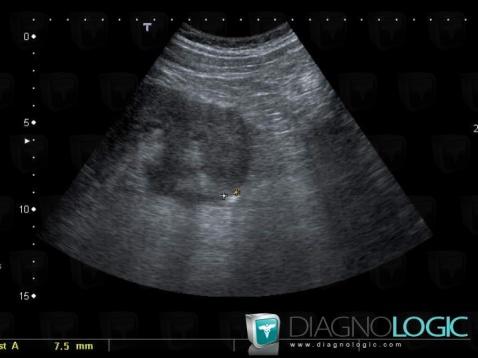

The images below illustrate this case for diagnoses Calculus, for the modalities (US)

Here is the specific information in the key image above:

- Diagnosis Calculus, Location(s) Ureter, with gamuts Ureteral filling defect